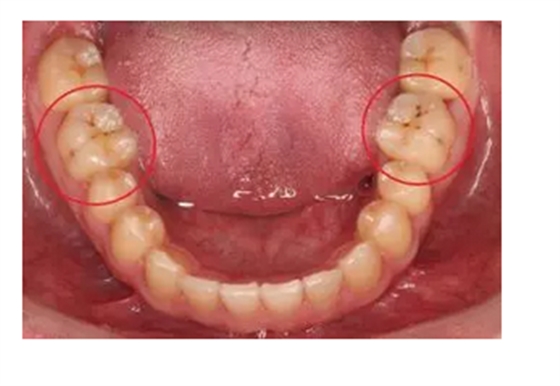

牙齒出現(xiàn)的齲壞,從外面看就表現(xiàn)為一個(gè)黑點(diǎn),通常位于窩溝點(diǎn)隙(牙面上點(diǎn)狀或線狀凹陷)。齲齒的罪魁禍?zhǔn)资强谇恢械哪承┘?xì)菌,但它們破壞牙齒也是需要時(shí)間的,從初期的變色到最終形成齲洞,通常需要1年半到2年。在此期間,我們多留心自己的牙齒,完全可能把齲壞扼殺在萌芽階段。如何才能及時(shí)發(fā)現(xiàn)這種隱匿的蛀牙呢?找位好牙醫(yī),半年檢查牙齒!

一旦確認(rèn)牙齒上的小黑點(diǎn)是齲齒就應(yīng)該盡早修補(bǔ),以阻止病變的發(fā)展。如果任由其繼續(xù)發(fā)展就會(huì)變成明顯的齲洞,這時(shí)患者會(huì)對(duì)冷熱酸甜等食物刺激敏感;當(dāng)損傷進(jìn)一步到達(dá)牙髓(即老百姓說(shuō)的“牙神經(jīng)”),就會(huì)疼痛難忍,嚴(yán)重影響日常生活。